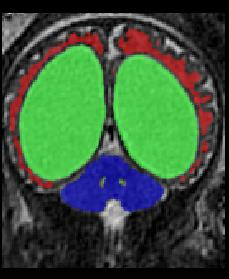

Limiting failures of machine learning systems is of paramount importance for safety-critical applications. In order to improve the robustness of machine learning systems, Distributionally Robust Optimization (DRO) has been proposed as a generalization of Empirical Risk Minimization (ERM). However, its use in deep learning has been severely restricted due to the relative inefficiency of the optimizers available for DRO in comparison to the wide-spread variants of Stochastic Gradient Descent (SGD) optimizers for ERM. We propose SGD with hardness weighted sampling, a principled and efficient optimization method for DRO in machine learning that is particularly suited in the context of deep learning. Similar to a hard example mining strategy in practice, the proposed algorithm is straightforward to implement and computationally as efficient as SGD-based optimizers used for deep learning, requiring minimal overhead computation. In contrast to typical ad hoc hard mining approaches, we prove the convergence of our DRO algorithm for over-parameterized deep learning networks with ReLU activation and a finite number of layers and parameters. Our experiments on fetal brain 3D MRI segmentation and brain tumor segmentation in MRI demonstrate the feasibility and the usefulness of our approach. Using our hardness weighted sampling for training a state-of-the-art deep learning pipeline leads to improved robustness to anatomical variabilities in automatic fetal brain 3D MRI segmentation using deep learning and to improved robustness to the image protocol variations in brain tumor segmentation. Our code is available at https://github.com/LucasFidon/HardnessWeightedSampler.